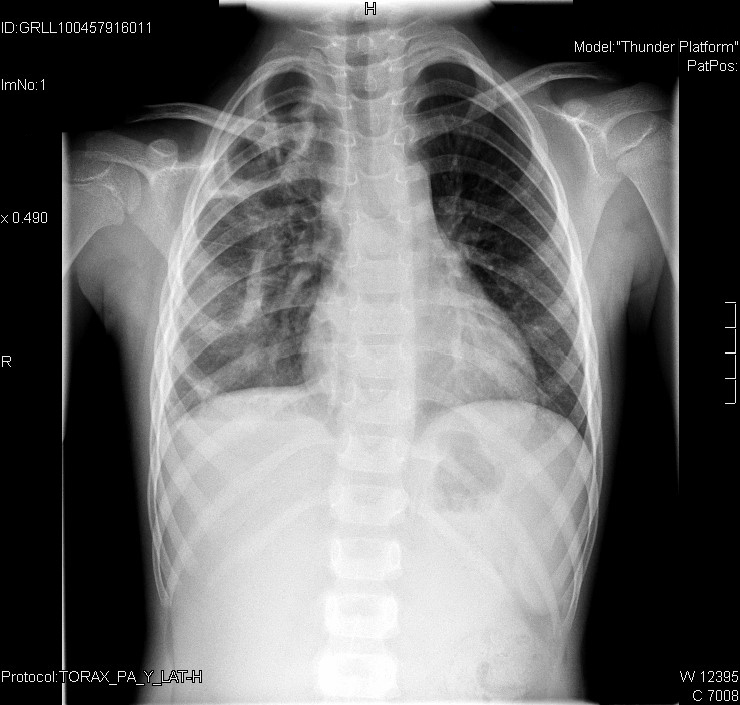

Tras 21 días de ingreso, nuestra paciente ya lleva afebril diez días y está completamente asintomática.

La analítica se ha normalizado (leucocitos 8,22 10E3/µl y PCR 3,2 mg/l) y la radiografía también presenta mejoría.